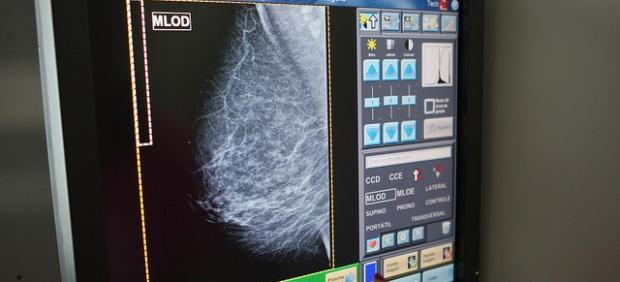

La británica Sarah Boyle, natural de la localidad inglesa de Stoke-on-Trent, tenía 25 años cuando los médicos le diagnosticaron cáncer de mama a finales de 2016, una noticia que supuso una auténtica conmoción y que la destrozó emocionalmente a ella y a toda su familia. Tras unos meses, después de una doble mastectomía y de varias sesiones de quimioterapia, los médicos se dieron cuenta que se habían equivocado en el diagnóstico y nunca había estado enferma.

Una vez detectado el error en julio de 2017, los facultativos explicaron a la paciente que su biopsia había sido almacenada de forma incorrecta y eso provocó la equivocación, según ha informado el diario británico The Sun.